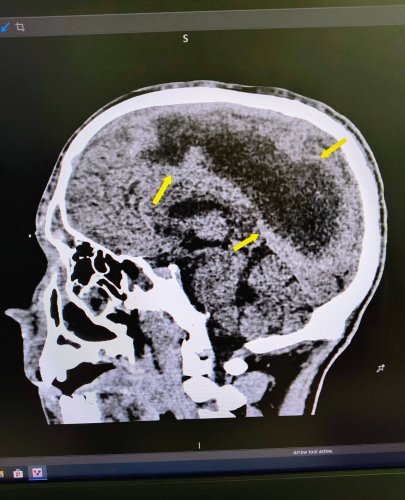

Однак одного дня матір знайшла сина не притомним на підлозі. Дитину одразу ж госпіталізували. “Пацієнт поступив до нас у стані глибокої коми. За даними КТ в дитини була емпієма, тобто масивне скупчення гною над правою півкулею головного мозку. Ми провели оперативне втручання, дренувавши вміст емпієми, тобто забрали гній з мозку”, — розповідає нейрохірург лікарні Святого Миколая Юрій Кузьмінський.